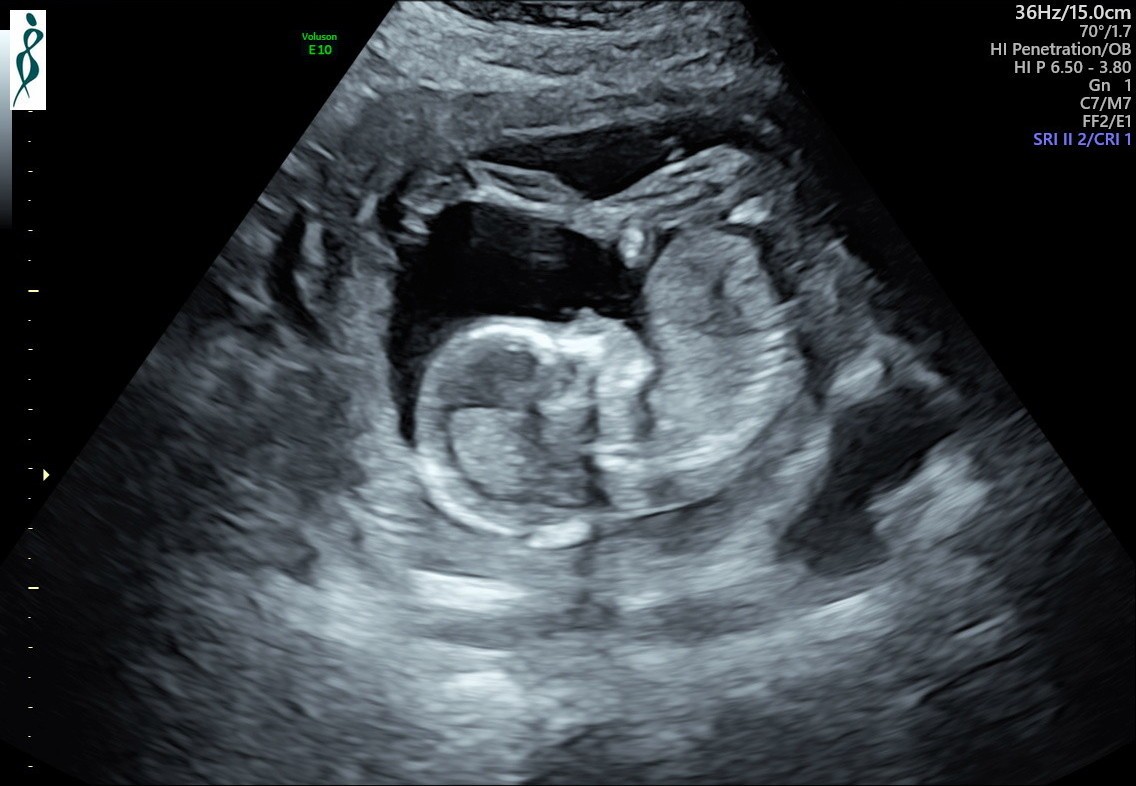

Hej Kobietki 🤗 Pchełka ma się doskonale 😁 Spała na początku badania i zasłaniała sobie buzię łapką, potem się troszkę rozruszała 💗 Jest taaaaaka śliczna 😭😍😭😍😭😍😭😍😭 Mój się przyznał, że też się strasznie denerwował przed tym USG. Teraz przez chwilę będziemy spokojni 😉 EF132B00-F0CA-46D0-918F-C9C1E6B94FED.jpeg6572E766-5AC9-4475-910D-935FEB244FE2.jpeg77D837DD-3B73-4015-919E-F6789011F490.jpeg